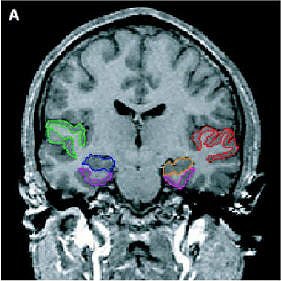

| Same subject. Above and below, axial MRI is used to present top-down views of the 3D reconstruction of the amygdala-hippocampal complex and parahippocampal gyrus. All images: Figure 1, Hirayasu Y, Shenton ME, Salisbury DF, et al. "Lower Left Temporal Lobe MRI Volumes in Patients with First-Episode Schizophrenia Compared with Psychotic Patients With First-Episode Affective Disorder and Normal Subjects," (Am J Psychiatry 1998; 155:1384-1391). |